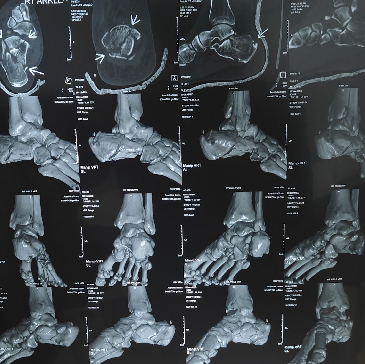

Hairline fractures occur when the bone develops a small crack but remains properly aligned. Most heal successfully without surgery through immobilization, rest, and regular monitoring.

• Diagnosis of minor bone cracks and stress fractures